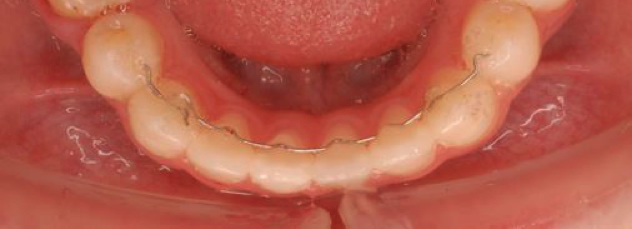

保定とは、矯正治療によって移動させた歯と顎の位置を、その位置で動かなくするために動いた部分の組織との調和をを図る処置のことです。

保定を成功させるためには、1本1本の歯の安定ばかりでなく、歯並びやかみ合わせさらには上下のあごの骨の位置から決まる、顎の顎間関係が安定できる条件を整えなければなりません。

すなわち、歯や歯周組織の調和を図るだけでなく、口の中の組織や顎の関節との調和、上下の歯が噛んだ時の当たり方やかみ合わせた時にかかる応力の分散、あごと顔の成長発育を誘導することをも考慮することが重要であると考えています。